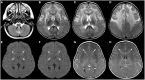

Macrocephaly affects up to 5% of the pediatric population and is defined as an abnormally large head with an occipitofrontal circumference (OFC) >2 standard deviations (SD) above the mean for a given age and sex. Taking into account that about 2-3% of the healthy population has an OFC between 2 and 3 SD, macrocephaly is considered as "clinically relevant" when OFC is above 3 SD. This implies the urgent need for a diagnostic workflow to use in the clinical setting to dissect the several causes of increased OFC, from the benign form of familial macrocephaly and the Benign enlargement of subarachnoid spaces (BESS) to many pathological conditions, including genetic disorders. Moreover, macrocephaly should be differentiated by megalencephaly (MEG), which refers exclusively to brain overgrowth, exceeding twice the SD (3SD-"clinically relevant" megalencephaly). While macrocephaly can be isolated and benign or may be the first indication of an underlying congenital, genetic, or acquired disorder, megalencephaly is most likely due to a genetic cause. Apart from the head size evaluation, a detailed family and personal history, neuroimaging, and a careful clinical evaluation are crucial to reach the correct diagnosis. In this review, we seek to underline the clinical aspects of macrocephaly and megalencephaly, emphasizing the main differential diagnosis with a major focus on common genetic disorders. We thus provide a clinico-radiological algorithm to guide pediatricians in the assessment of children with macrocephaly.